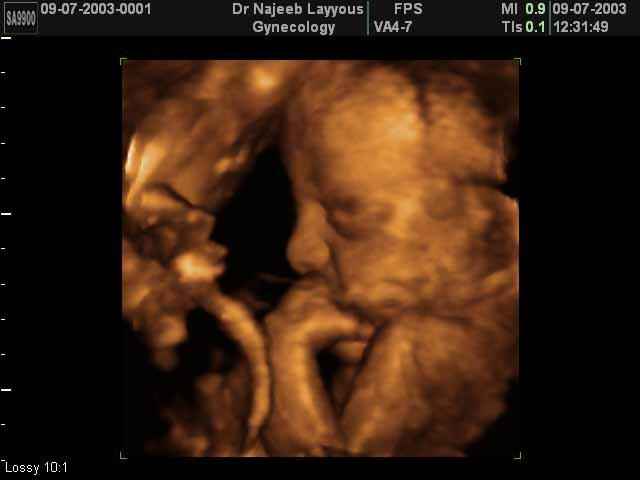

- صور جانبية لرأس الجنين

صور جانبية لرأس الجنين بجهاز الالتراساوند ثلاثي الأبعاد | الدكتور نجيب ليوس